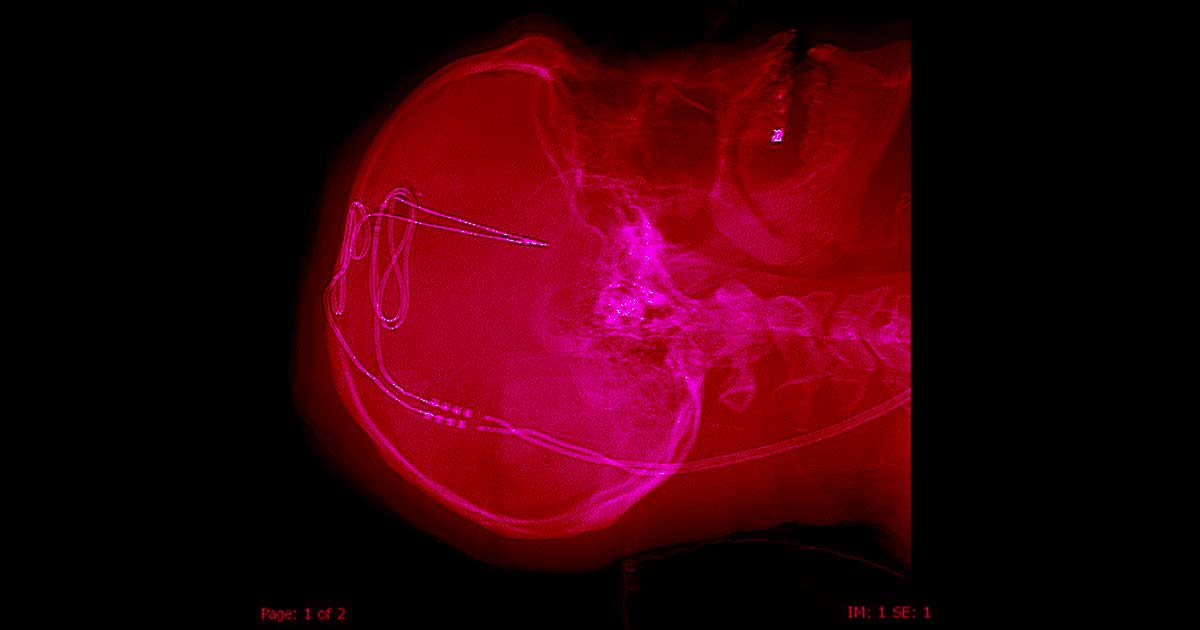

Unfortunately, none of the treatments worked — and that’s why Buckhalter decided to let neurosurgeon Ali Rezai drill a hole in his skull and implant an electrode into his brain in November.

By electrically stimulating the part of the brain that regulates impulses, Rezai and his team at the West Virginia University Rockefeller Neuroscience Institute think they might be able to help Buckhalter and three other participants in a new trial control their opioid cravings.